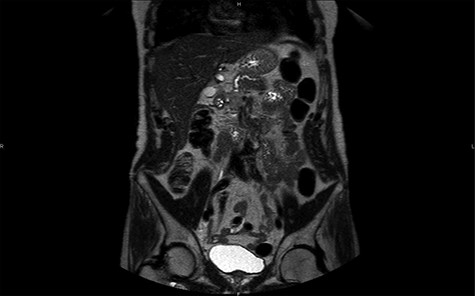

Magnetic resonance imaging (MRI) confirms the hypervascularized and atypical character of this pancreatic tumor (Figs 2 and 3). Moreover, one hepatic lesion with the same characteristics is highlighted.

MRI in axial section, phase T1 + gadolinium: visualization of a structure with hypersignal at the level of the head of the pancreas.

MRI in coronal section, T2 phase: visualization of a compression of the main pancreatic duct.